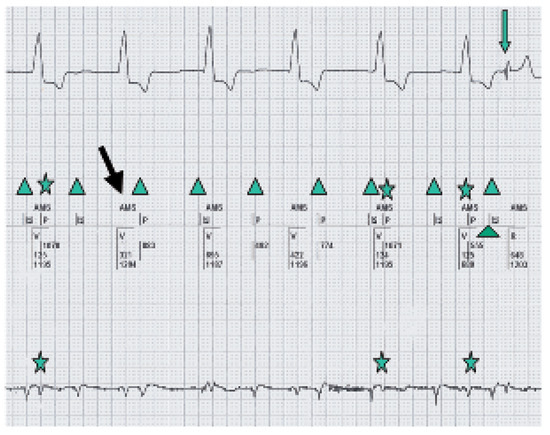

A Difficult Pacemaker ECG Resulting in an Unnecessary Intervention

by Peter Gnehm and Beat Schaer

Cardiovasc. Med. 2006, 9(6), 227; https://doi.org/10.4414/cvm.2006.01177 - 30 Jun 2006

Viewed by 61

Abstract

We report on a 67-year-old patient with coronary artery disease, presenting with dyspnea and chest pain. The pacemaker ECG of the patient was difficult to read in the emergency setting. Sudden changes in the heart rate were misinterpreted as a non-sustained ventricular tachycardia, [...] Read more.

We report on a 67-year-old patient with coronary artery disease, presenting with dyspnea and chest pain. The pacemaker ECG of the patient was difficult to read in the emergency setting. Sudden changes in the heart rate were misinterpreted as a non-sustained ventricular tachycardia, and the paced ventricular rhythm was misread as ST-segment elevation. The combination of an inadequately programmed pacemaker, a patient with panic attacks and a misleading ECG interpretation lead to an unnecessary coronary angiography. We discuss how erroneous episodes of incorrect mode switching due to atrial far field sensing with rate drops can be avoided by correct pacemaker testing. Full article